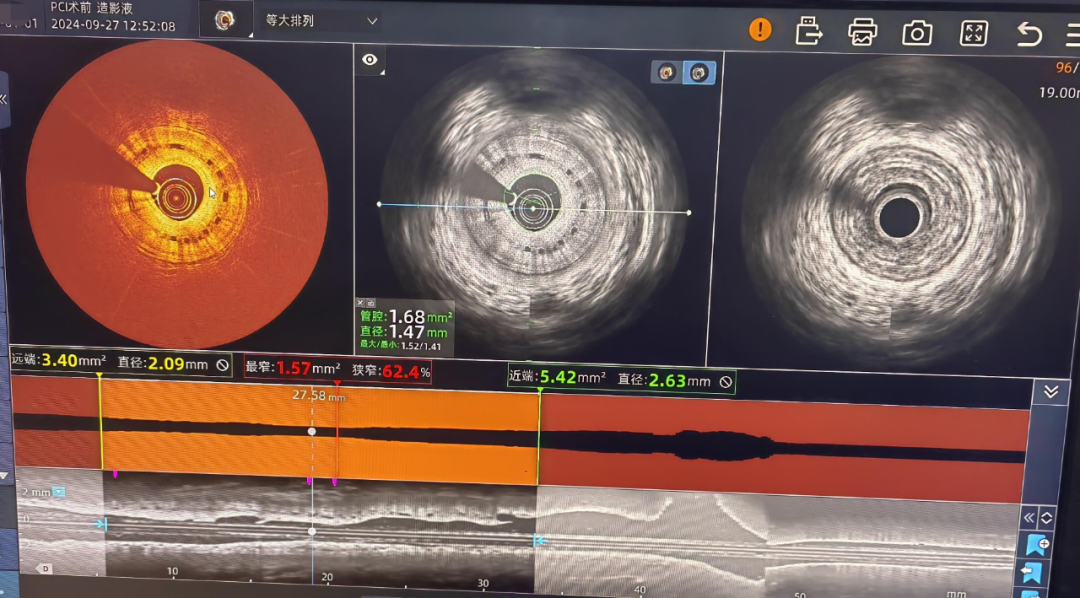

病例1:通过IVUS-OCT一体化成像精准判断长迂曲病变斑块性质、精准测量管腔面积。PCI术后再次行IVUS-OCT判断支架膨胀贴壁良好。

病例2:青年男性,外院可吸收支架后再狭窄。通过IVUS-OCT一体化成像精准判断支架完整性、降解程度、再狭窄病变性质、精准测量管腔面积。

IVUS-OCT一体机是全新的血管内成像设备,完全由我国自主创新研发,利用一根导管、一次扫描成像,同时完成IVUS、OCT两项血管内影像检查,实现IVUS和OCT的图像优势互补。该系统不仅图像清晰,成像速度快,测量精准,运行稳定,可切换4种成像模式(单IVUS成像、单OCT成像、IVUS-OCT同时同屏、IVUS-OCT同步融合成像),不仅看的清,而且看的深,满足临床的多样化需求,精准评估,优化介入。